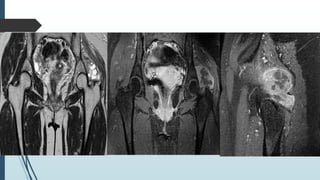

20 yrs. female with left hip pain , x-ray shows lucency over left greater

trochanter

Presenting caseX-ray

T1 T2

PD T1 C+ GRE

Extraskeletal Mesenchymal Chondrosarcoma